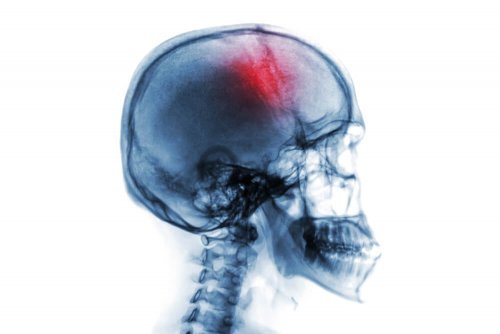

Apoplexia: fatores de risco e sintomas

A apoplexia é uma síndrome neurológica súbita que consiste em uma hemorragia ou perda de circulação sanguínea no cérebro.

Quando o suprimento de sangue não atinge o cérebro corretamente o tecido cerebral morre. Isso resulta em um déficit neurológico que pode ser uma causa de incapacidade ou morte.

Na verdade, o termo apoplexia se refere simplesmente a um sangramento ou ruptura sanguínea em qualquer órgão. Desta forma, existem numerosos traços, dependendo do órgão a que se referem. No entanto, quando a palavra é usada sozinha, geralmente se refere a um acidente vascular cerebral.